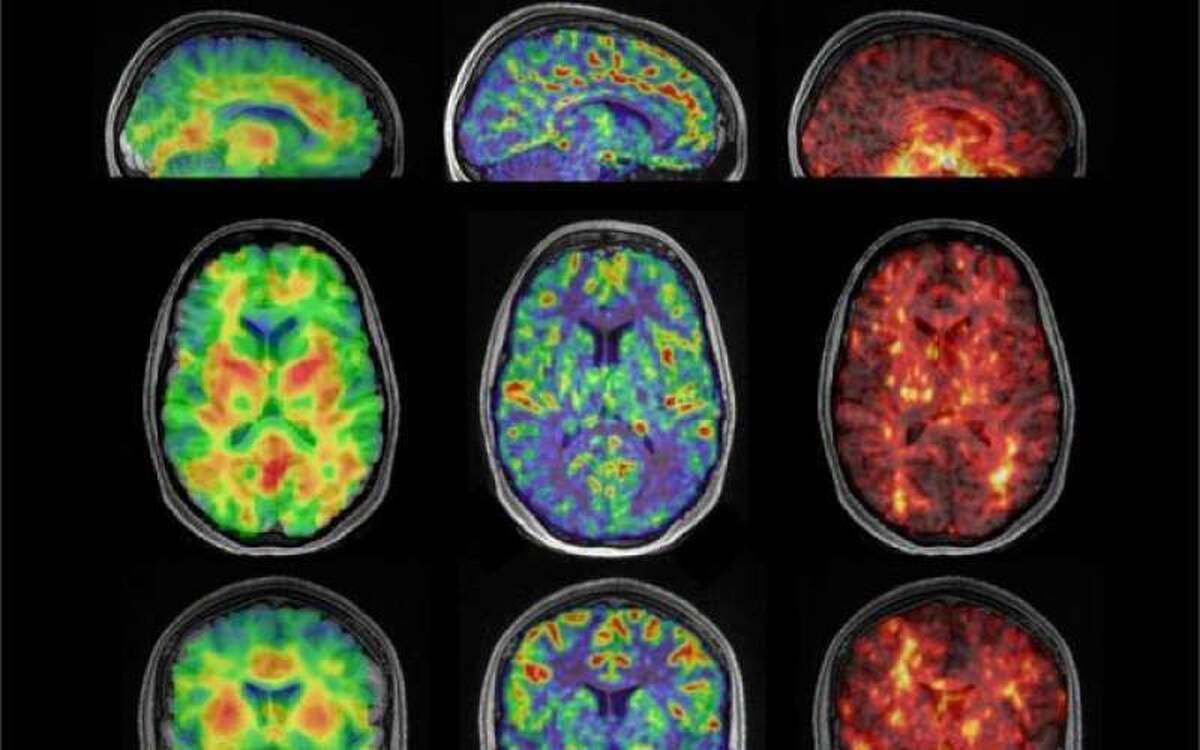

متخصصان مغز ۱۷ داوطلب بین ۲۲ تا ۳۵ سال را با استفاده از الاستوگرافی تشدید مغناطیسی (MRE) اسکن کردند. MRE که تصویربرداری تشدید مغناطیسی (MRI) را با امواج صوتی ترکیب می‌کند، اطلاعاتی را برای ایجاد تصاویر دقیق از سطوح مختلف سفتی در مغز به متخصصان ارائه می‌دهد.

متخصصان گفتند: ما از طریق MRE می‌خواستیم بفهمیم که چگونه جریان خون می‌تواند به طور بالقوه بر سفتی مغز تأثیر بگذارد. هیپوکامپ تنها بخشی از مغز است که این رابطه بین جریان خون و سفتی را نشان می‌دهد.